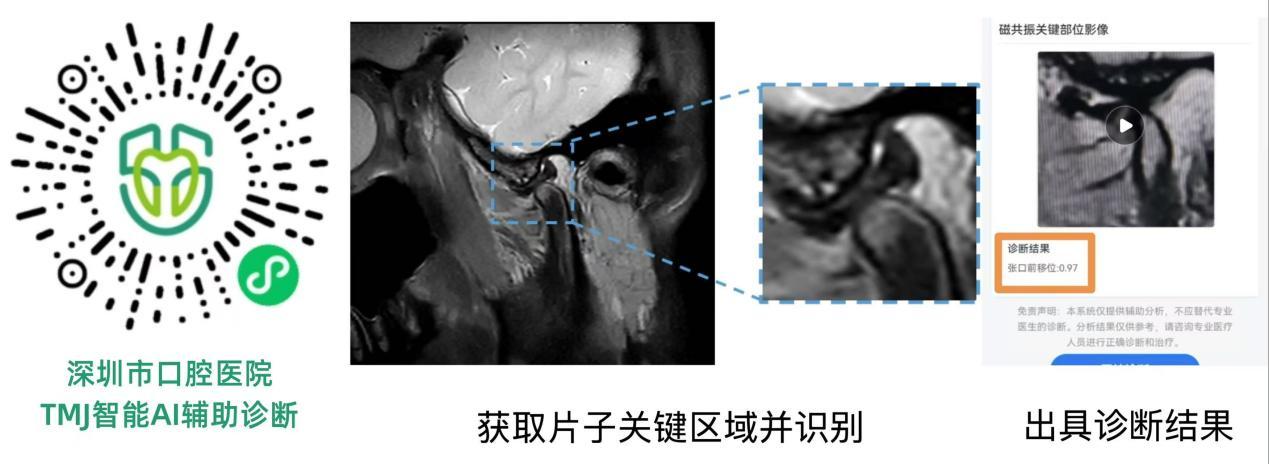

本次大会上,由深圳市口腔医院朱耀旻主任医师和于跃副主任医师牵头研发的“AI辅助颞下颌关节MR影像诊断APP”首次亮相。作为全国首家引进磁共振设备的口腔专科医院,深圳市口腔医院在过去三年间系统收集并整理了逾3万例颞下颌关节MR影像数据,为AI研发奠定了坚实的数据基础。

据介绍,该应用通过大样本、高质量的真实世界数据进行深度学习模型训练,能够辅助医生更高效、客观、精准地判读颞下颌关节盘前移位等关键MR影像特征,有望解决广大基层医生在影像判读中的实际困难。